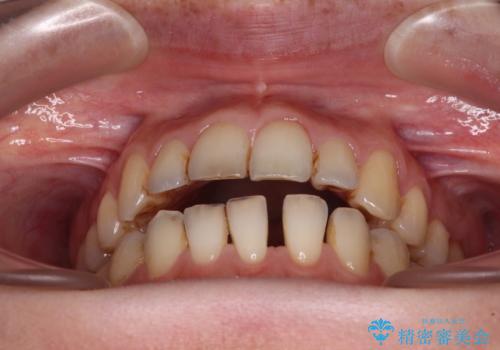

- 上下前歯の隙間を気にして来院された患者様です。

下顎前歯が1本欠損しており、上下小臼歯はクロスバイトとなり、上下前歯の接触もないという不正咬合の状態でした。

クロスバイトはワイヤー矯正が得意とするところであり、上下前歯の非接触や開咬はインビザラインの得意とするところであるので、ワイヤー装置により事前にクロスバイトを改善し、その後にインビザラインにて仕上げていくこととしました。